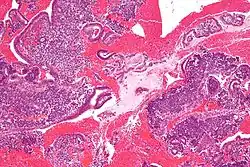

-

Endometrioid adenocarcinoma from biopsy. H&E stain. -

Micrograph of decidualized endometrium due to exogenous progesterone. H&E stain. -

Micrograph showing endometrial stromal condensation, a finding seen in menses.